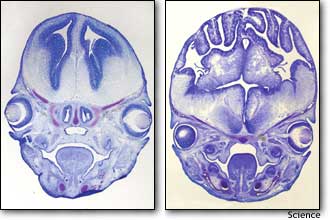

А так мы должны писать скучно-научно. В результате продолжительных генетических экспериментов в Гарвардской медицинской школе в Бостоне группа ученых под руководством доктора Кристофера Уолша (Christopher Walsh) сумела создать мышей с мозгами, во много раз превышающих обычные.

Впрочем, вторая фраза все-таки немного ближе к истине. Действительно, Уолш и компания проводили эксперимент с веществом, которое называется бета-катенин, и каким-то образом сумели задеть ген, отвечающий за мозги. Если вы думаете, что из инкубатора вылез слюнявый монстр с черепом, равным по объему уолшеву, остыньте, это не так. Просто обычно гладкий мышиный мозг оказался у подопытных с извиланами — то есть, он вырос настолько, что его пришлось переупаковывать. Кстати, если бы мозг человека не был так плотно утрамбован, нам бы понадобилась бы просто гигантская голова. Просто гигантская. Не всем, разумеется.